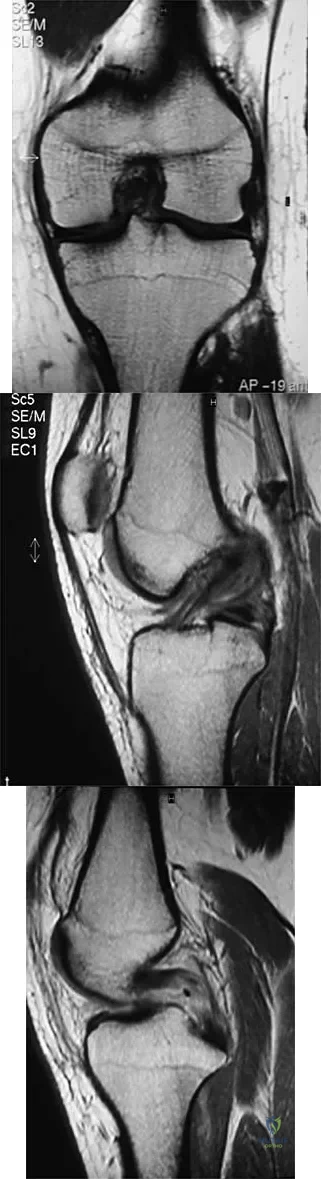

A 35-year-old woman who is a recreational runner reports posterior knee pain and tightness in the knee with flexion during running. She denies any history of trauma. Examination reveals normal patellar glide and tilt and no patellar apprehension. Range of motion is 5 degrees to 120 degrees, and quadriceps function and knee ligamentous examination are normal. Radiographs are normal. An MRI scan is shown in Figure 18. What is the most likely diagnosis?

Explanation